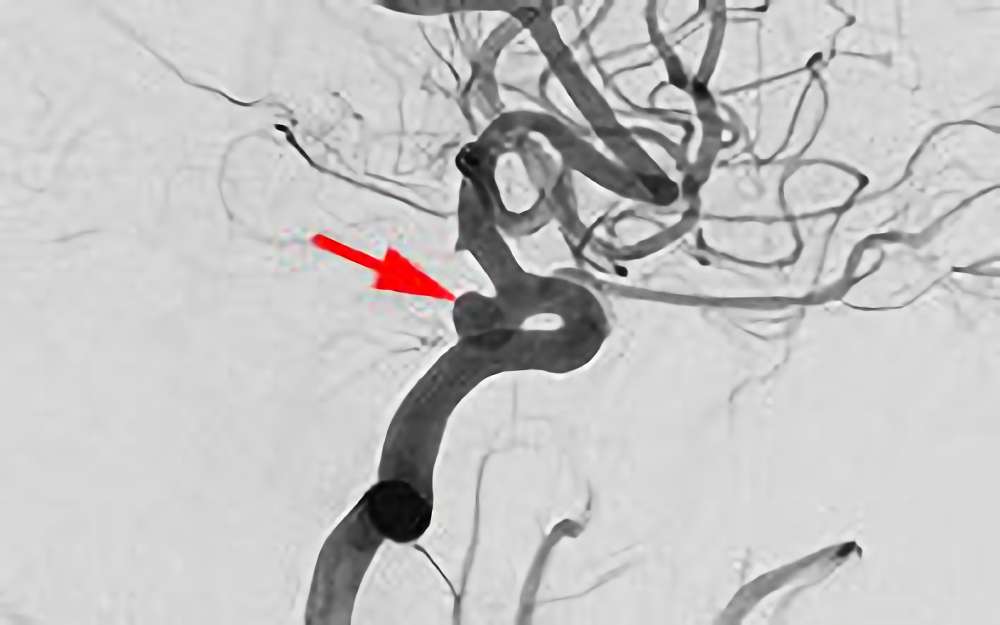

No.1628 手術前